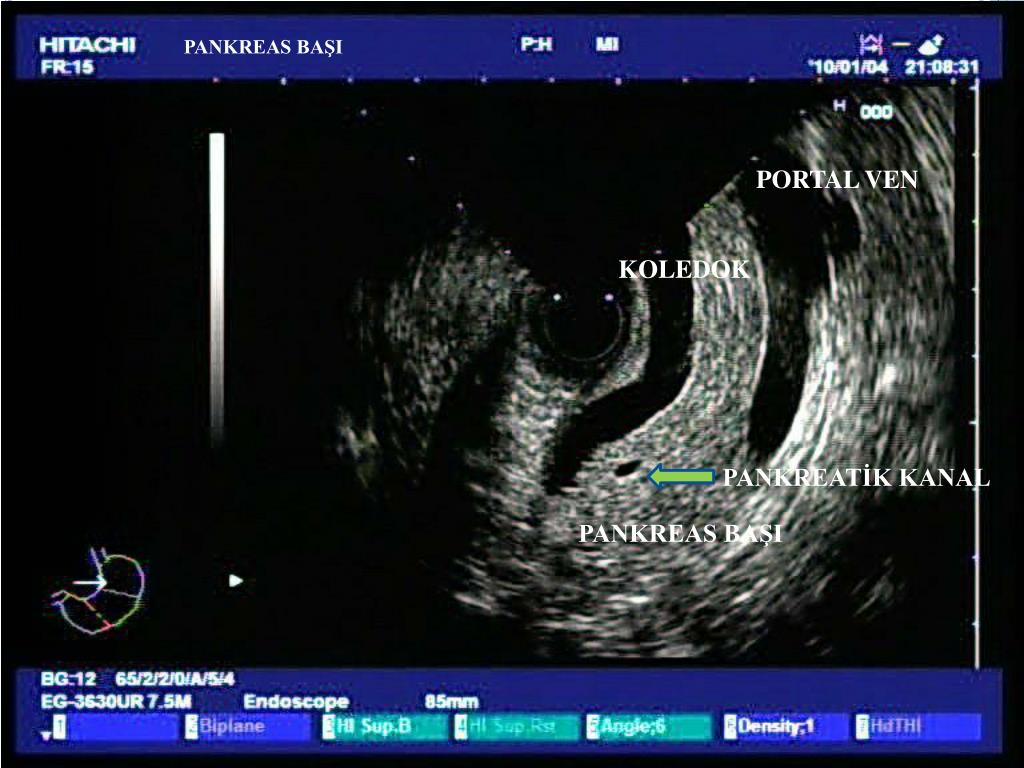

8. PANKREAS BAŞI PORTAL VEN KOLEDOK PANKREATİK KANAL PANKREAS BAŞI